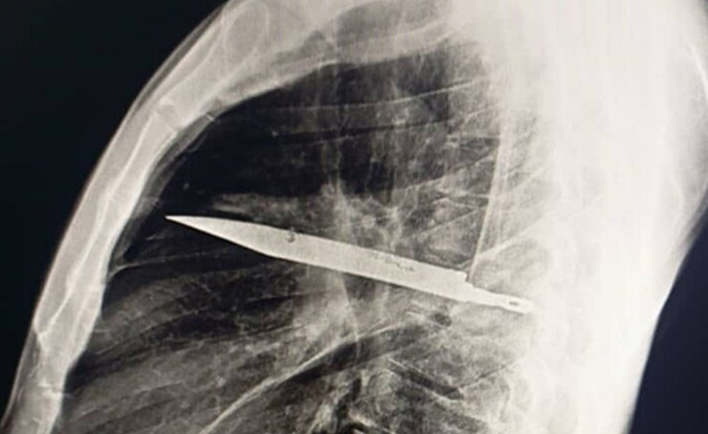

ونشر أطباء مستشفى موهيمبيلي الوطني في تنزانيا مؤخرًا دراسة حالة غير عادية في مجلتهم العلمية “المكتبة الوطنية للطب”. وشرحوا حالة رجل يبلغ من العمر 44 عامًا يتمتع بصحة جيدة بشكل عام جاء إلى المستشفى بتاريخ طويل من إفرازات صديدية بيضاء من حلمة ثديه الأيمن. وقال التقرير أن المريض أنكر أي ألم في الصدر أو صعوبة في التنفس أو سعال أو حمى، لكنه سُئل عما إذا كان لديه أي شيء جدير بالذكر ليخبر الأطباء، فتذكر مشاجرة عنيفة قبل ثماني سنوات، أصيب خلالها بعدة جروح في وجهه وظهره وصدره وبطنه، حيث تمكن الأطباء من خياطة الجروح آنذاك، وعاش حياة هادئة في الغالب منذ ذلك الحين، حتى بدأت حلمة ثديه تفرز صديدًا. ولم يتمكن الأطباء من تحديد السبب، فأمروا بإجراء فحص بالأشعة السينية، ليصدموا برؤية نصل سكين ضخم عالق في صدر الرجل. وكتب الأطباء في دراسة الحالة: “أظهر التصوير الأولي بالأشعة السينية الجانبية للصدر وجود جسم معدني عالق في منتصف الصدر، مع وجود تعتيم محيط به، يُحتمل أن يُمثل ورمًا دمويًا موضعيًا مزمنًا أو تليفًا ما بعد الصدمة، وهو أحد مضاعفات طعنة المريض“.

وبطريقة ما، تمكنت نصل السكين، الذي دخل من خلال لوح الكتف الأيمن، بأعجوبة من تفادي أي أعضاء رئيسية. في وقت مشادة الرجل، قبل ثماني سنوات، لم يكن لدى المستشفى الذي عولج فيه أي وسيلة لإجراء فحص إشعاعي، ولأنه لم يُبلغ عن أي ألم بعد شفاء جروحه، لم يُكلف أحد نفسه عناء إجراء المزيد من التحقيقات. والأغرب من ذلك أن السكين لم يُسبب للمريض البالغ من العمر 44 عامًا أي إزعاج لفترة طويلة. لكن القيح كان ناتجًا عن تراكم الأنسجة الميتة حول الجسم الغريب. وبعد هذا الاكتشاف المروع، تم استخراج السكين بعناية أثناء الجراحة مع الأنسجة الميتة والقيح. وأمضى المريض 24 ساعة في وحدة العناية المركزة قبل نقله إلى الجناح العام لعشرة أيام أخرى. وسارت عملية تعافيه على ما يرام، وكانت المتابعات اللاحقة خالية من أي مشاكل.